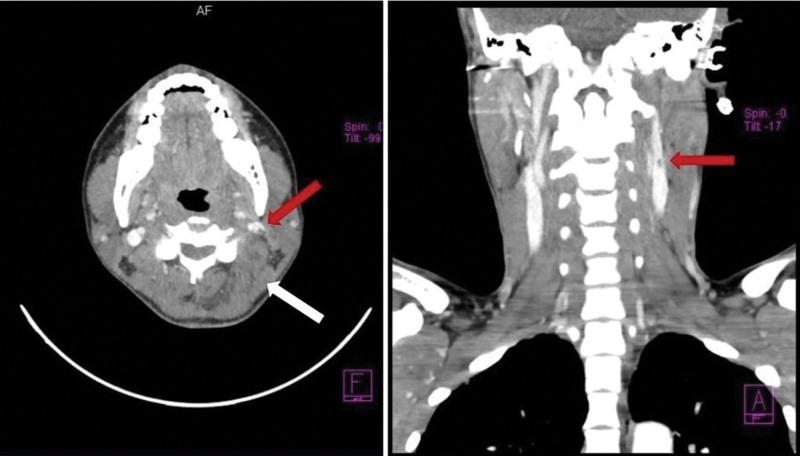

A 31-year-old woman from California, United States (US), was admitted to the emergency room with a history of 2 days of fever and severe throbbing pain in the left cervical region. Thorax and neck CT tomography revealed confluent cavities suggestive of septic embolism in the lungs and a filiform thrombus in the lumen of the left internal jugular vein, with moderate swelling of the soft and muscular tissues. Methicillin-resistant Staphylococcus aureus (MRSA) was isolated from the blood culture.

The thrombus in the internal jugular vein associated with cellulitis in the neck and multiple cavitary lesions in the lungs support the diagnosis of LLS caused by MRSA with septic embolization.